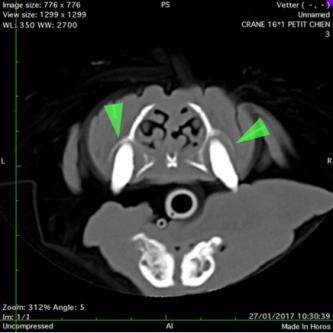

Otite moyenne: bulle tympanique opaque